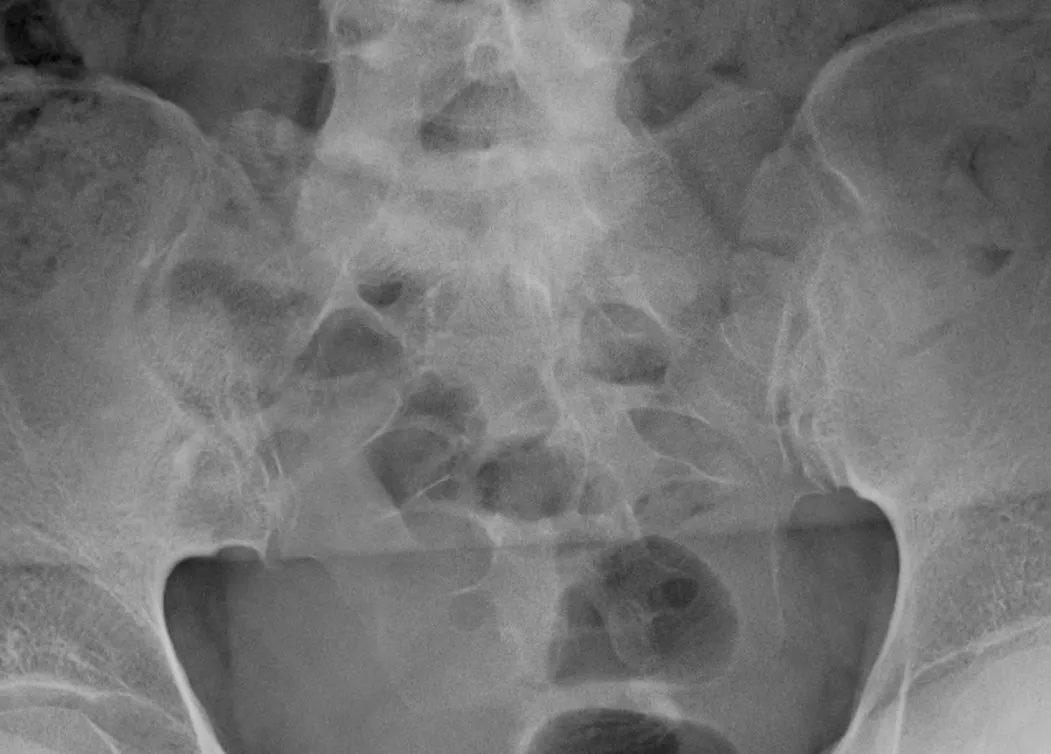

一方、下位胸椎-腰椎MRIではT2 STIR画像でL5とS1の椎体に骨髄浮腫を認め、その他の椎体辺縁にもT2延長病変を認めた(写真5)。

写真5 下位胸椎-腰椎MRI